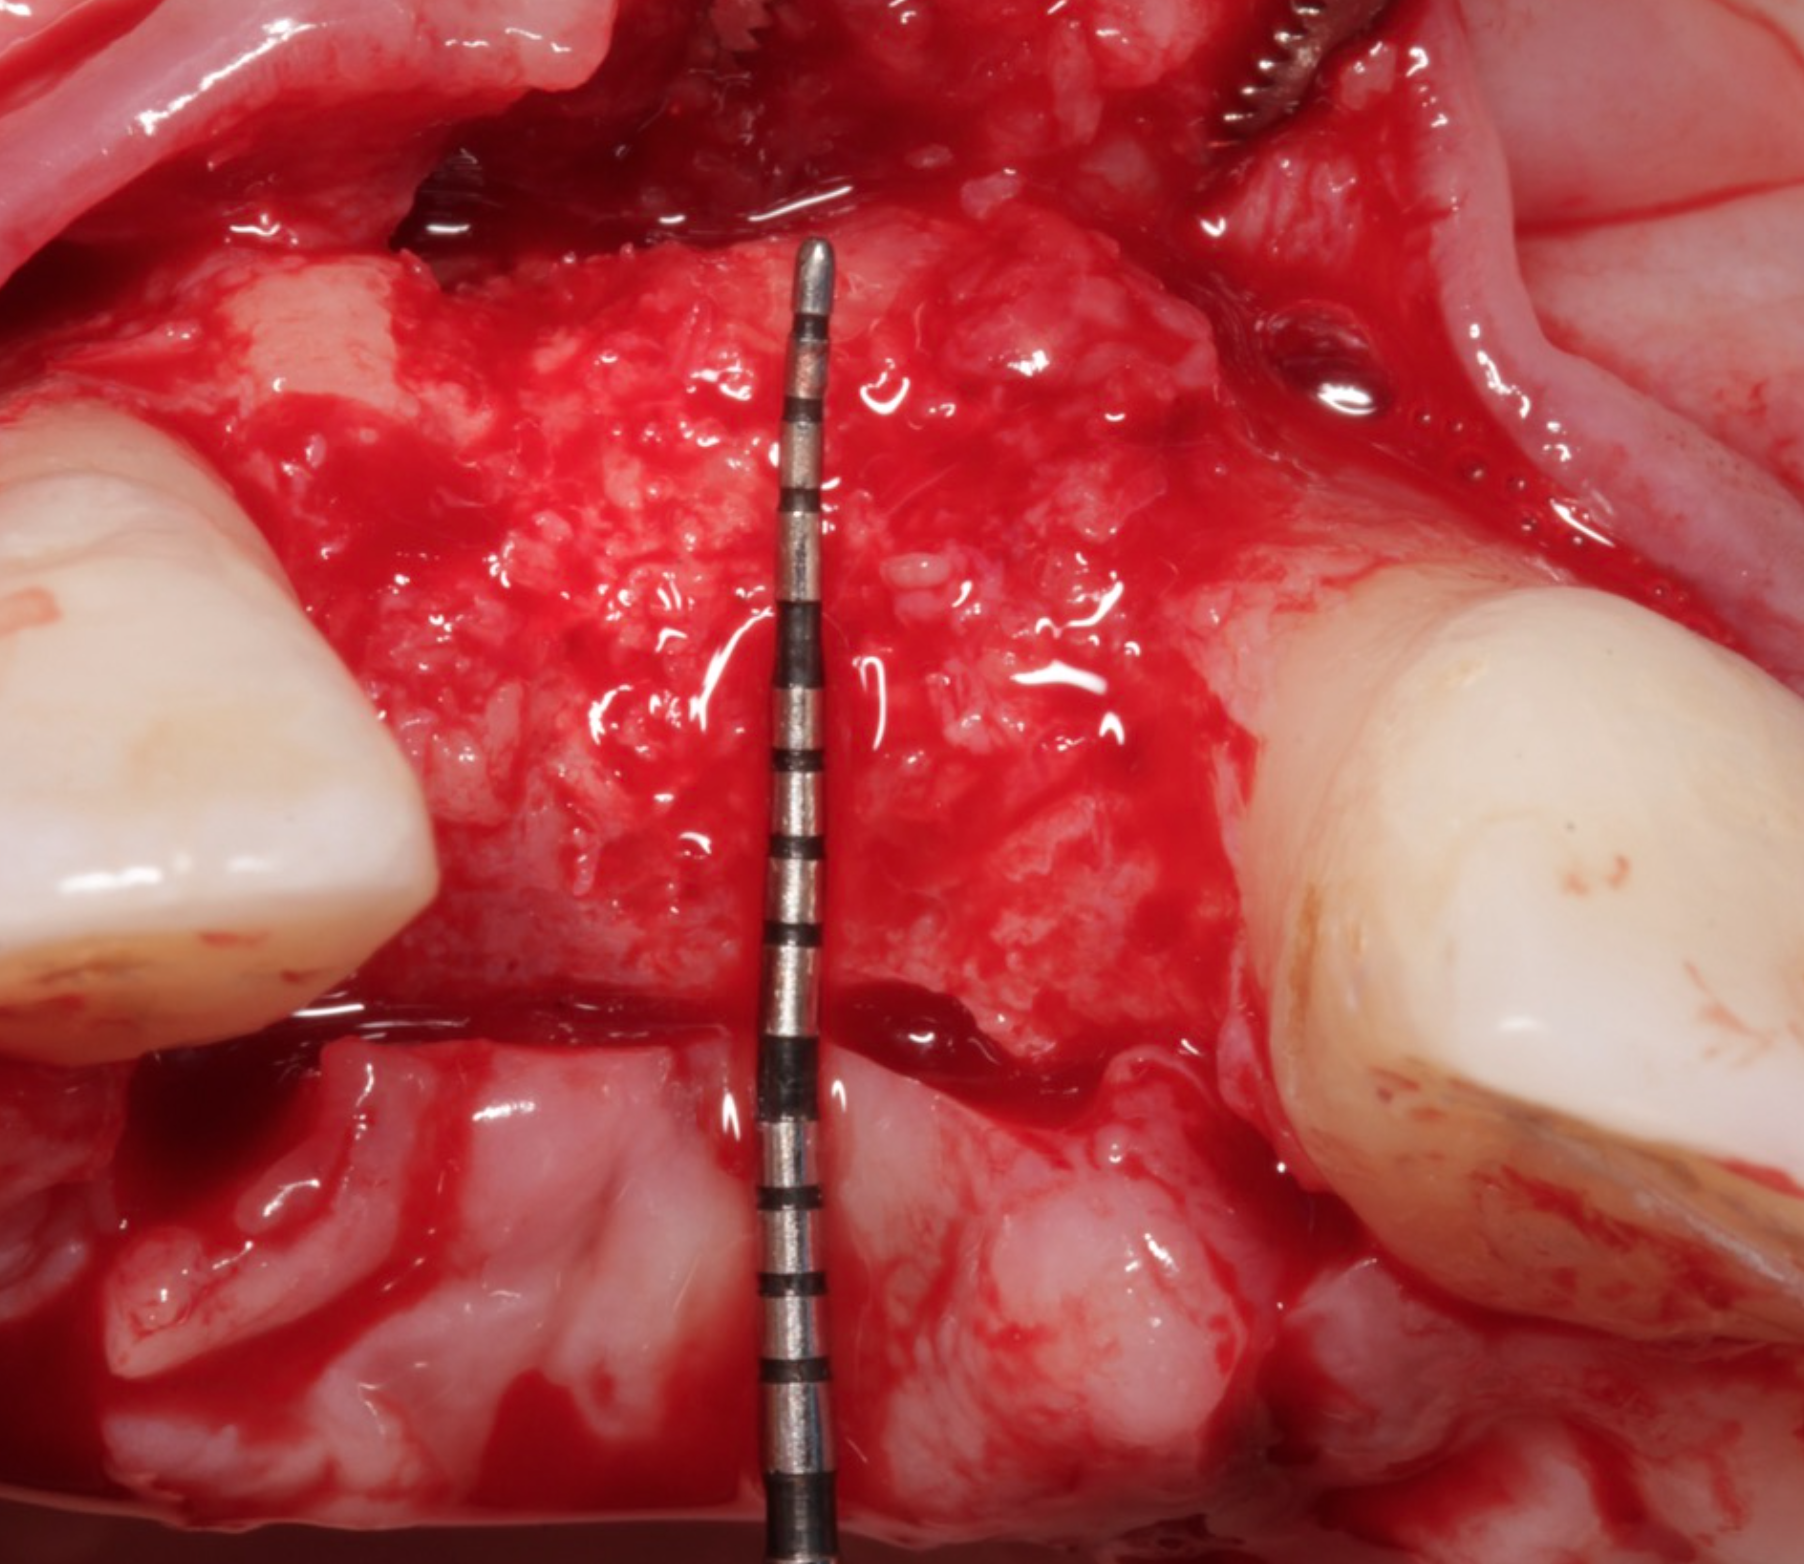

To address this, Dr. Nik employed the Sausage Technique, as described by Dr. Istvan Urban, for effective bone regeneration. During the first stage, bone augmentation was performed using a Ti-reinforced, non-resorbable dense PTFE membrane, combined with a mixture of autogenous bone particles and Mineross allograft from Biohorizons Camlog UK. After 7 months of smooth and successful healing, Dr. Nik placed a Conelog Progressive implant, supplemented by additional bone grafting with a resorbable striate and collagen membrane using the Mini Sausage Technique to ensure enhanced bone stability.

• Implant placement